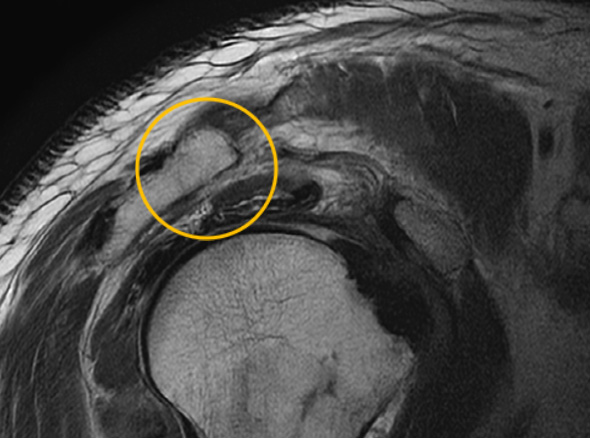

어깨충돌증후군이 발생하게 되면 회전근개에 염증이 발생하게 되고

급성 부종을 일으키게 됩니다.

30대를 시작으로 50대까지 증상이 지속적으로 악화되고 통증도 점차 커집니다.

증상이 심한 경우 일상 생활에 어려움이 발생되어 수술적인 치료를 고려할 수 있습니다.